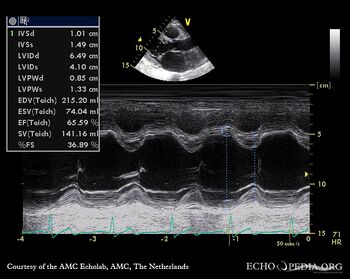

PSAX: thickend aortic valve M-Mode: dilated left ventricle